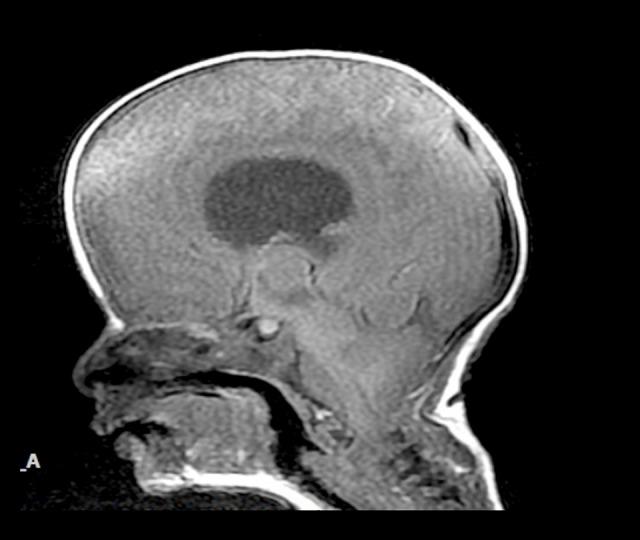

BACKGROUND Arthrogryposis multiplex congenita is a multifactorial syndromic or non-syndromic group of conditions consisting of multiple congenital contractures of the body, of unknown etiology. It is associated with a heterogenous group of disorders that include but are not limited to processes such as myopathic and neuropathic. Neural tube defect is a neuropathic disorder that incorporates myelomeningocele that might be either isolated or within a spectrum of multiple diseases. CASE REPORT This is a case report of a 28-day-old male born with lower limb arthrogryposis with myelomeningocele and Chiari II malformation in a Mediterranean population. CONCLUSIONS Lower extremity arthrogryposis with myelomeningocele and Chiari II malformation is a prenatal diagnosis that requires high clinical suspicion, early multidisciplinary intervention, and genetic counselling. As long as new approaches are being explored in the management of such cases, babies born now with neural tube defects can expect better quality of life.

https://cdn.ncbi.nlm.nih.gov/pmc/blobs/0c0f/6537754/b839a8049ab8/amjcaserep-20-719-g001.jpg